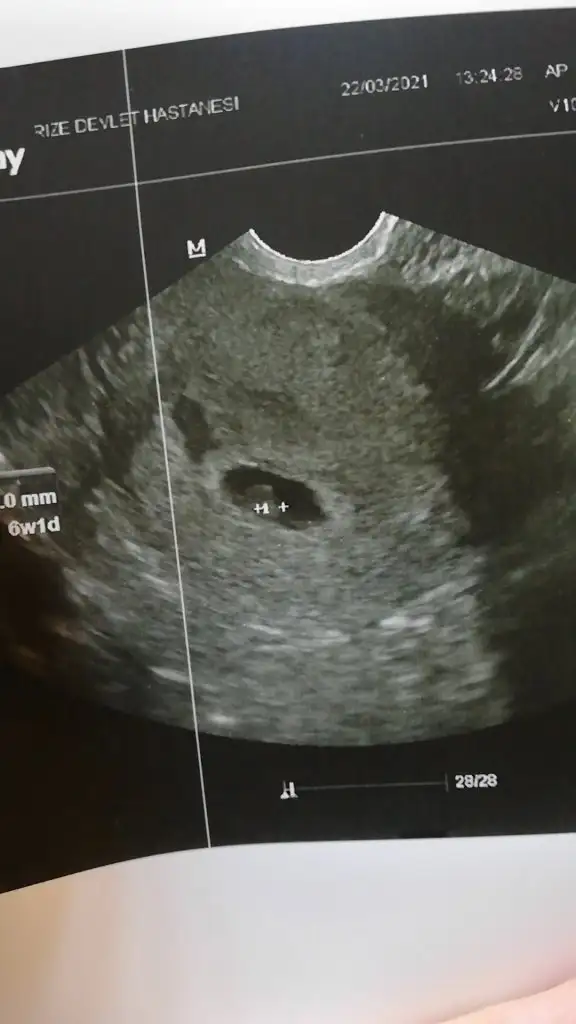

Allah tamamına erdirsinBiz geldik teyzelerrr, tam 6 haftalığız, bugün kalp atışını duydukDarısı başınıza hadi bu ayyy bereketli geçsin inşş

Bu arada ultrasyon vajinal ultrasyon

Ayyy maşallah subhanallahBiz geldik teyzelerrr, tam 6 haftalığız, bugün kalp atışını duydukDarısı başınıza hadi bu ayyy bereketli geçsin inşş

kız bu bebek erkek bence çünkü kız bebeklerin keselerinin yuvarlak erkeklerin keselerininse daha uzun ince fasülye gibi yada oval olduğunu söylemişlerdi.Biz geldik teyzelerrr, tam 6 haftalığız, bugün kalp atışını duydukDarısı başınıza hadi bu ayyy bereketli geçsin inşş